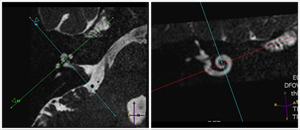

MRI imaging of the inner ear

Cochlear Nerve Inferior vestibular nerve Superior vestibular nerve Facial Nerve Scala tympani Scala tympani Scala tympani Scala tympani Spiral lamina Spiral lamina Spiral lamina Spiral lamina Scala vestibuli Scala vestibuli Scala vestibuli Scala vestibuli